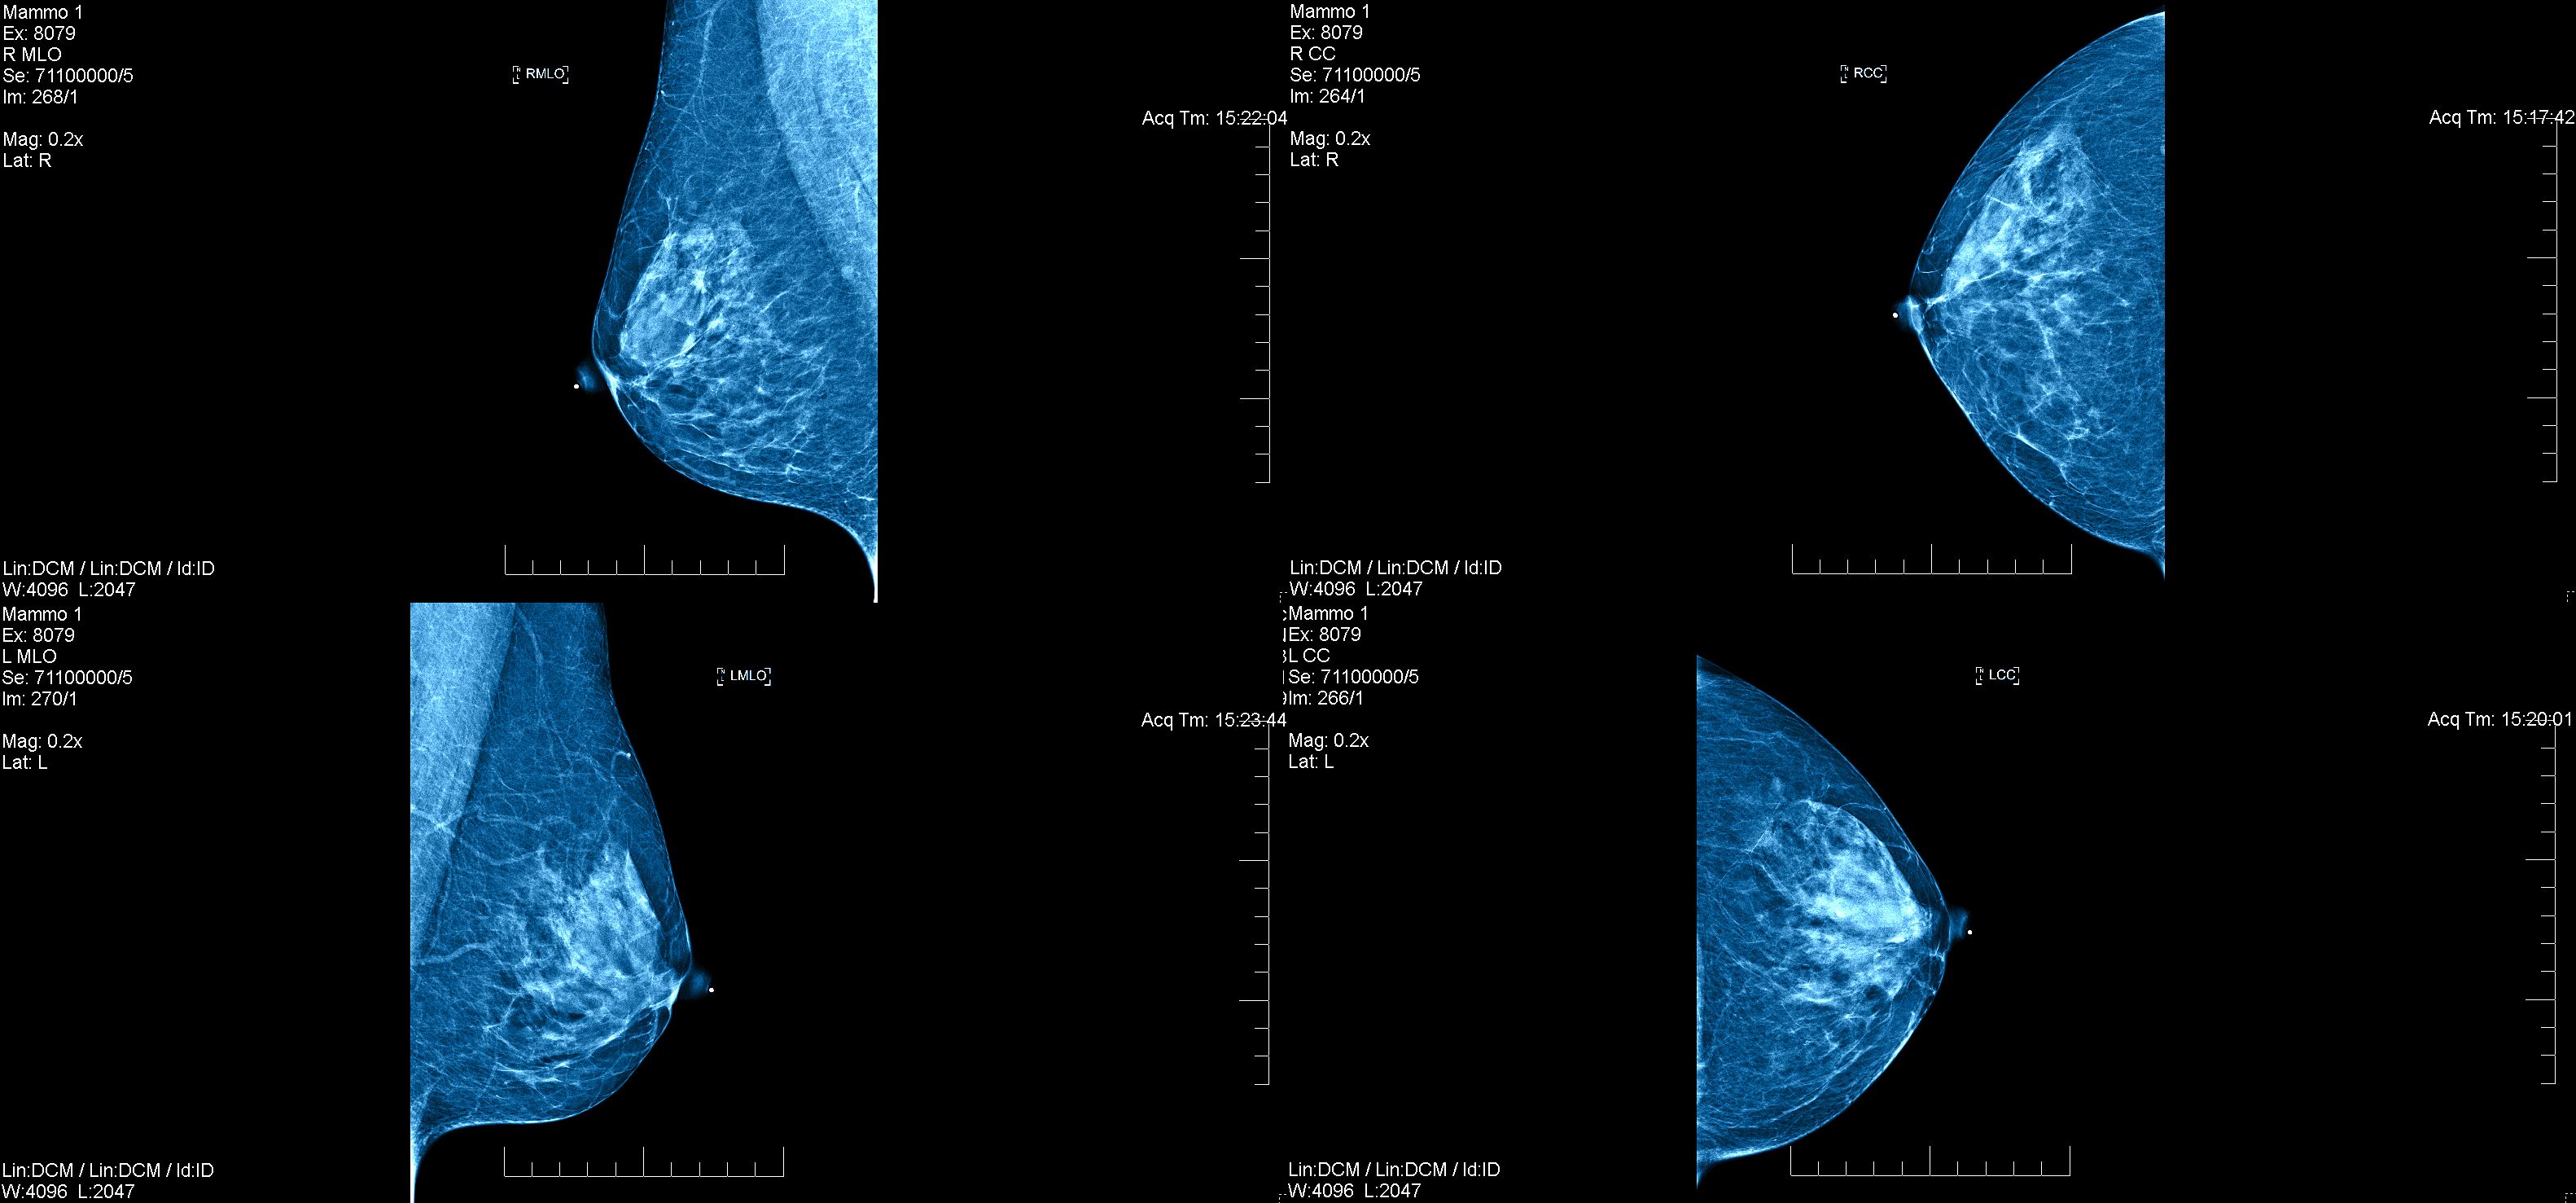

Esistono diversi metodi per la diagnosi precoce del cancro al seno. Tra questi, la mammografia è uno degli strumenti più efficaci. È raccomandato che le donne sopra i 40 anni si sottopongano a una mammografia annuale o biennale.

Oltre alla mammografia, l'ecografia e la risonanza magnetica possono essere utilizzate per ulteriori indagini soprattutto in casi di seni densi o per monitorare lesioni sospette. Questi strumenti diagnostici, se utilizzati correttamente, possono rilevare il cancro al seno in fasi non palpabili.